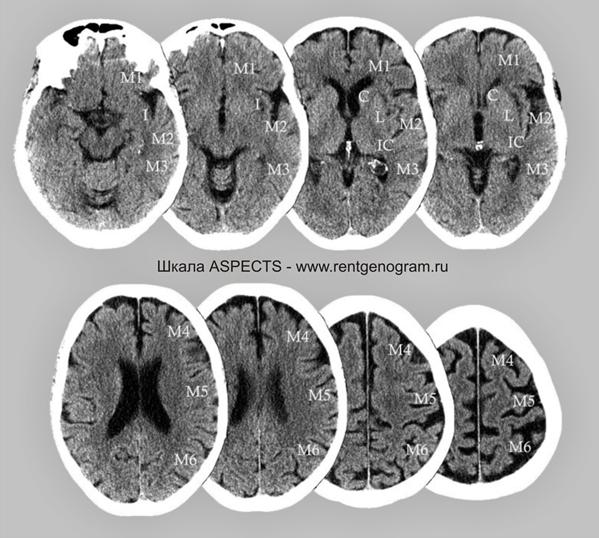

Оценка по шкале ASPECTS

При наличии симптомов ОНМК в первые часы болезни проводилось КТ головного мозга. Для количественной оценки ранних ишемических изменений использовалась шкала ASPECTS (Alberta Stroke Programme Early CT Scale).

Сосудистая зона средней мозговой артерии (СМА) делилась на 10 участков: лентикулярное ядро (L), хвостатое ядро (C), внутренняя капсула (IС), кора островка (I) и 6 зон бассейна СМА – М1, М2, М3, М4, М5, М6. Каждая зона оценивалась в 1 балл (всего 10 баллов). Для оценки учитывались такие проявления, как локальная гиподенсивность мозга. Полное отсутствие изменений на КТ в бассейне СМА соответствовало 10 баллам, в то время как тотальное поражение — 0 баллов.